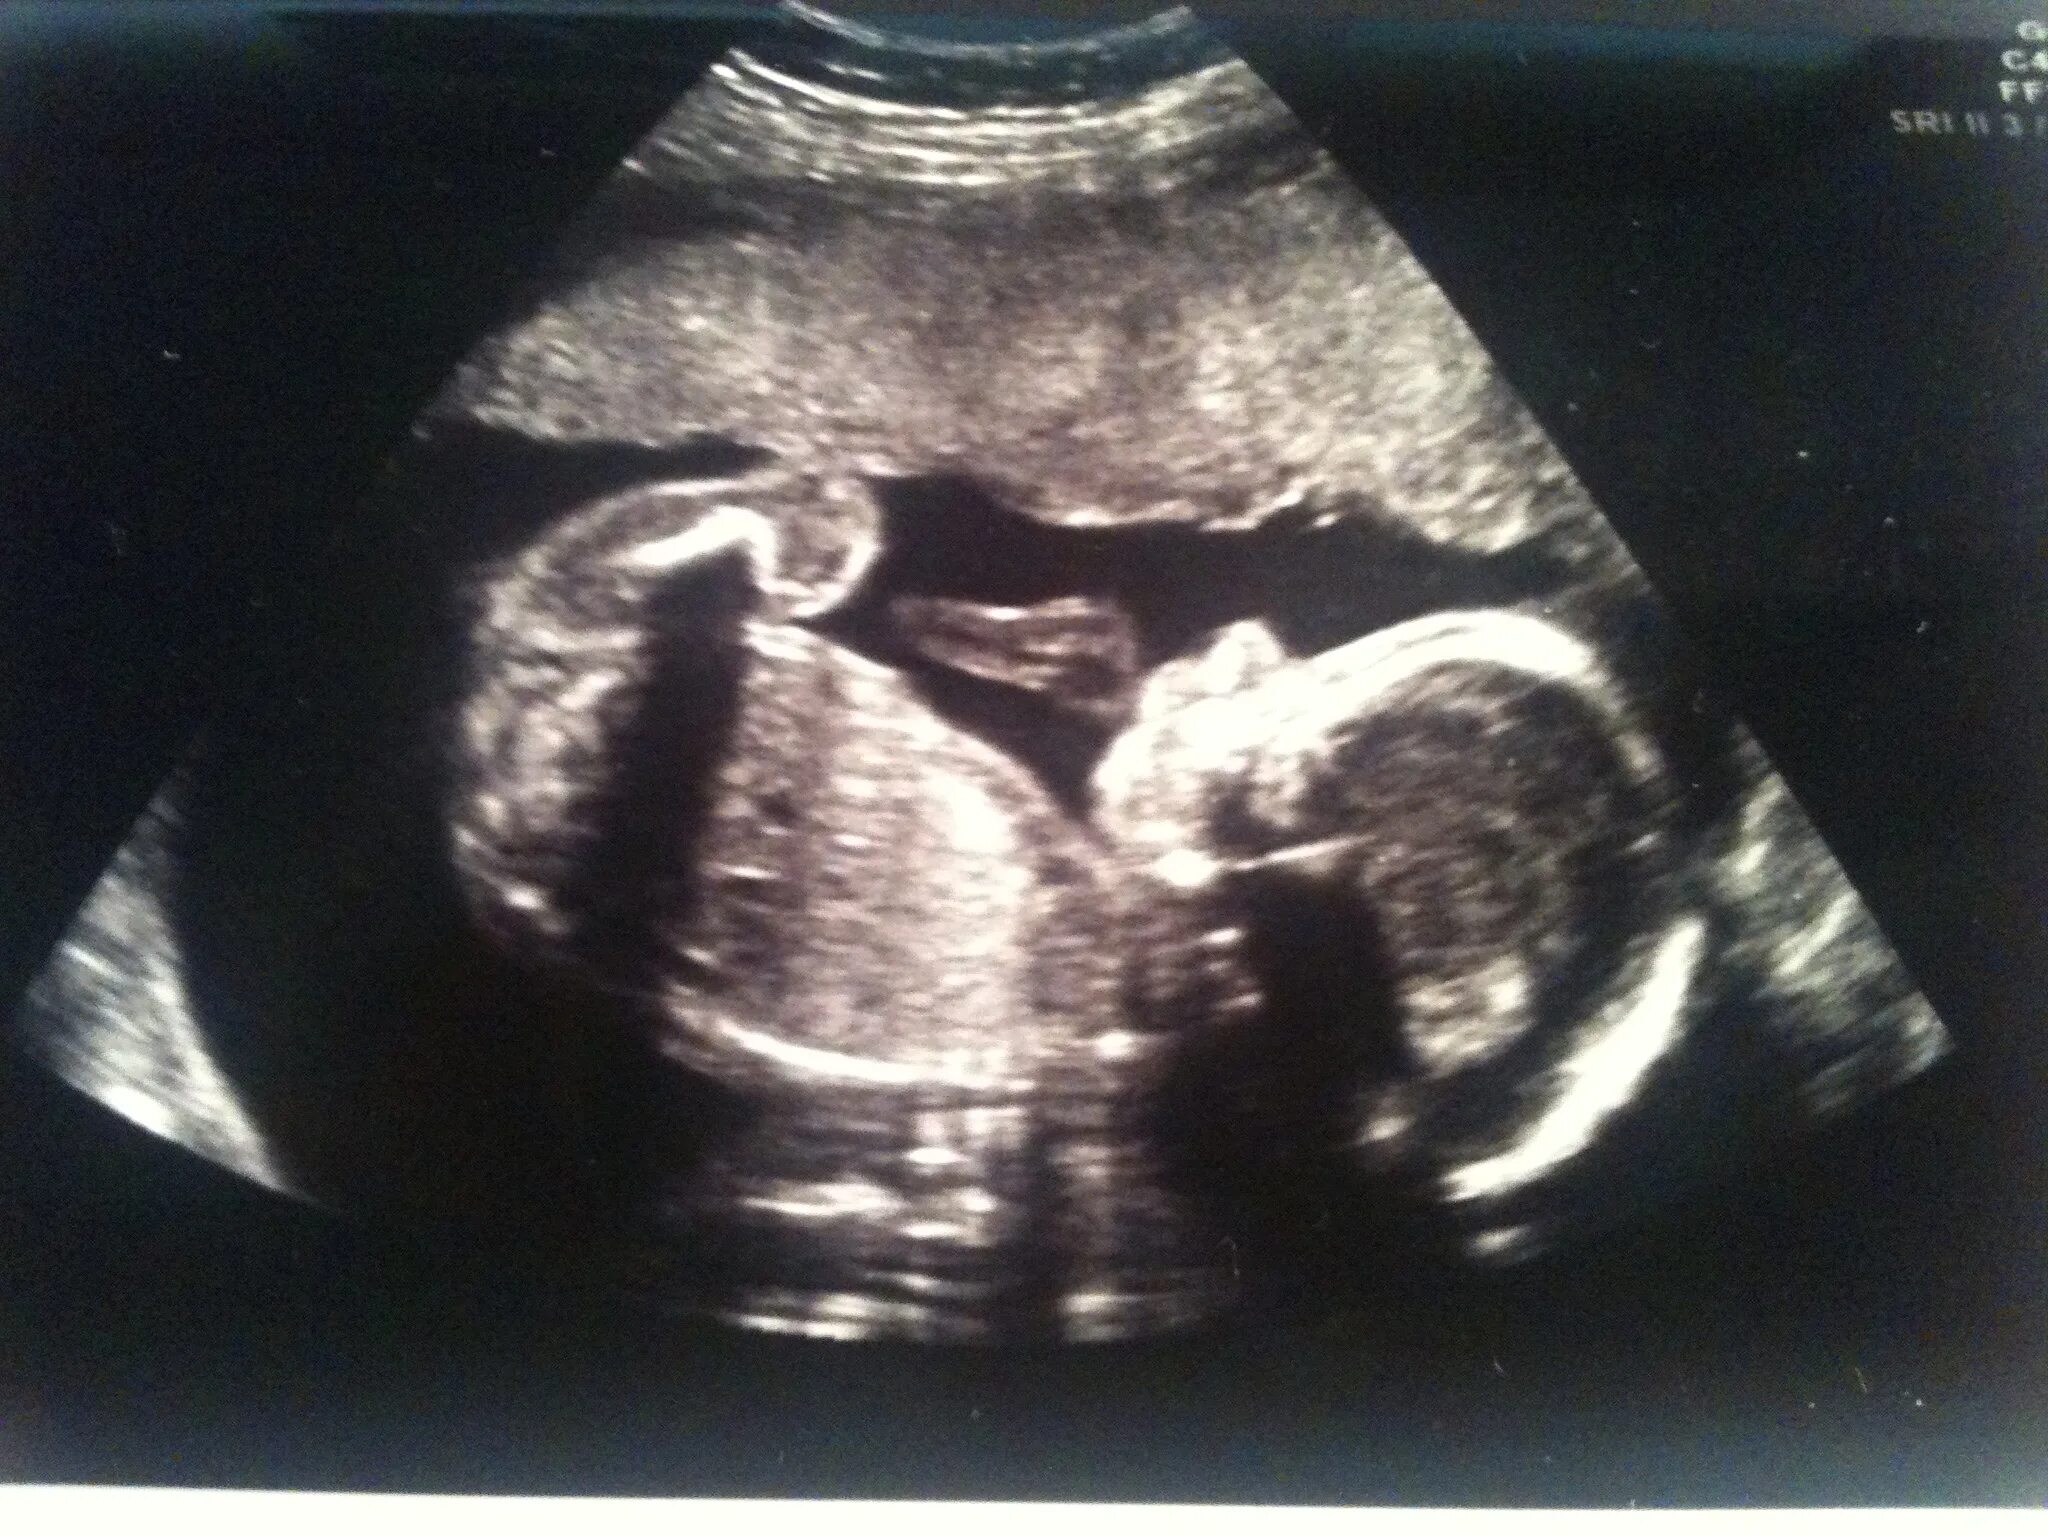

25 недель 2 дня